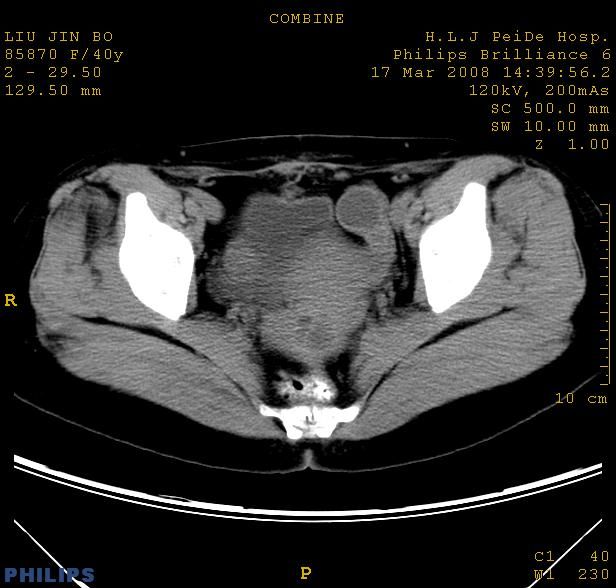

以下是引用qiuleiyu在2008-4-27 12:36:00的发言:[br]支持;右侧腰大肌后方神经源性肿瘤可能大,神经节细胞瘤?

以下是引用形影不离在2008-4-27 14:11:00的发言:[br]1.考虑右侧腰大肌脓肿。[br]2.左侧附件区炎症。[br]3.子宫增大,建议:进一步检查。